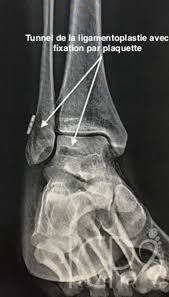

Instabilite De Cheville Dr Julien Batard

visitez l'article complet ici : https://www.orthopedie-montpellier.fr/instabilite-de-cheville/